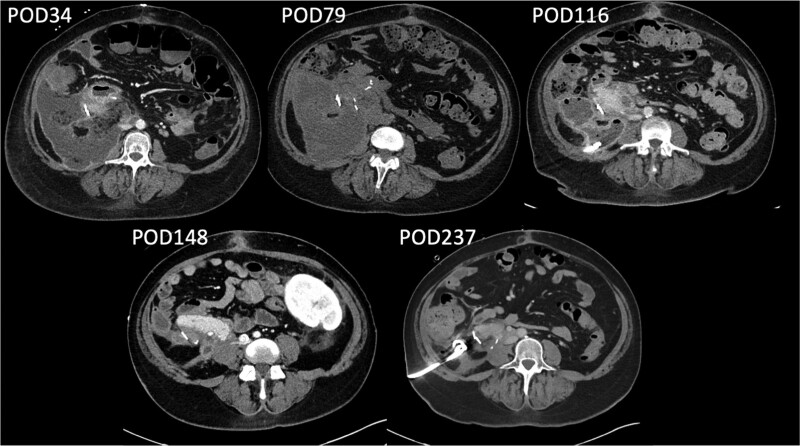

Video-assisted Retroperitoneal Debridement for Graft Pancreatitis.